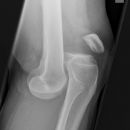

Traumatische Epiphysenlösung

Traumatische Luxation